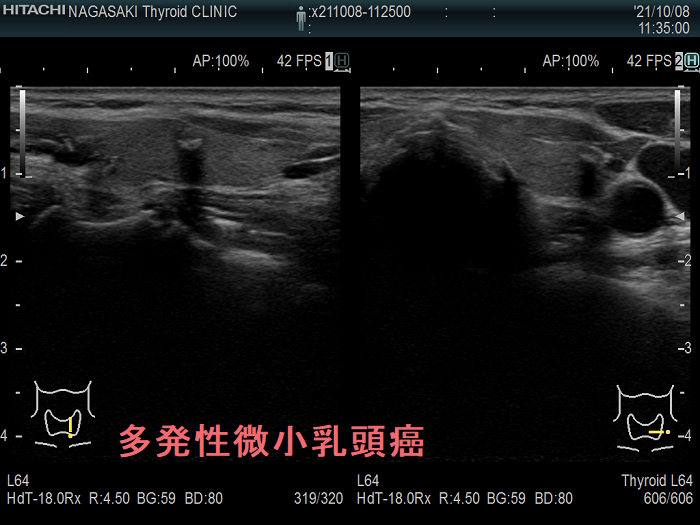

多発性の甲状腺微小乳頭癌

多発性の甲状腺微小乳頭癌は、リンパ節転移しやすいとされます(Am J Surg. 2014 Sep;208(3):412-8.)。

- 海外では、①両葉多発性の場合、②甲状腺癌の家族歴(遺伝性)がある場合、甲状腺微小乳頭癌であっても甲状腺全摘が推奨されます[アメリカ甲状腺学会(American Thyroid Association:ATA)やヨーロッパ分子癌学会(European Society of Molecular Oncology:SMO)のガイドライン](Thyroid. 2016 Jan;26(1):1-133.)(Ann Oncol. 2019 Dec 1;30(12):1856-1883.)(下記)